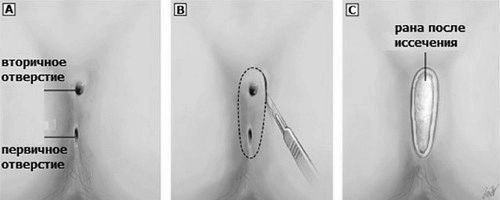

Оперативне втручання з видалення свища куприка

Як було сказано раніше, всі мазі, компреси і примочки дають лише тимчасовий ефект, і тільки хірургічним способом, що передбачає видалення всіх наявних відгалужень, можна повністю вилікувати пацієнта від даного захворювання.

При оперативному втручанні здійснюється розтин порожнини кісти і чистка її від гнійного накопичення. Далі, пацієнт проходить реабілітацію. Так як рана буде відкрита, то потрібне постійне відвідування лікарів і перев'язувального кабінету. Крім цього, необхідно дотримання певного режиму, а також процедур по догляду. Протягом реабілітаційного періоду хворому заборонено піднімати тяжкості і вести активний спосіб життя, а також переохолоджуватися і перебувати на сильній спеці.

При збереженні запального процесу лікарі вдаються до повторної чищенні рани. Хворий в середньому знаходиться в стаціонарі протягом двох місяців. Працездатність відновлюється через місяць після проведення операції.

Операція з видалення епітеліального куприкового ходу. Обов'язкова при лікуванні, тільки так гарантовано повне зцілення

Видалення свища куприка, рубцевих тканин здійснюється під анестезією виключно після припинення течії запального процесу. Тільки цей захід допоможе уникнути рецидиву захворювання - кіста куприка. Симптоми і лікування після їх виявлення вимагають прийняття оперативних заходів.

Первинне і вторинне отвір при перебігу запального процесу. При висічення розкривається вся площа від першого до другого для чищення від гною і видалення кісти